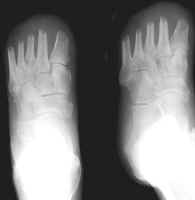

The images above demonstrate a transmetatarsal amputation through all five digits.

The bone edges are beveled and there is a generous soft tissue pad.